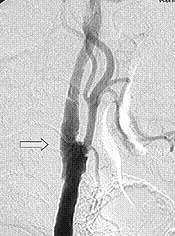

| 術前 | 術後 |

| →部分の血管のつまり(術前)をとり、血液が太く流れているのがわかる(術後)=脳血管造影 | |

アテローム硬化性脳梗塞は、首や脳内の太い動脈がひどく狭くなったりつまったりしているために、脳に送り込まれる血液量が減って脳梗塞をおこすもので す。一般に前記のような内服薬だけでは症状の進行や再発を予防できないことも多く、その場合には血液の量を増やすために外科的な治療が必要となります。

首の頸動脈が非常に狭いときは、直接血管を切開

して中のアテロームを取り出す血栓内膜剥離術を行ないます(写真)。